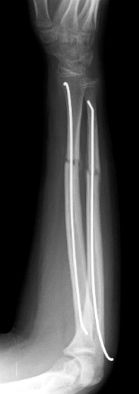

Las fracturas de ambos huesos del antebrazo al mismo nivel, con líneas de fractura oblicua-transversa o desplazamiento convergente son inestables y precisarán de tratamiento quirúrgico. En estos casos está indicado, dependiendo de la edad del paciente, el tratamiento mediante reducción y osteosíntesis. El enclavado intramedular elástico es el tratamiento de elección (Figura 15).

Figura 15: a-Imagen clínica de fractura de antebrazo derecho con gran deformidad. b- Radiografía donde se aprecia fractura de radio-cúbito de trazo transverso en el mismo nivel. c, d-Enclavado intramedular elástico. e,f- Imagen final con buena consolidación ósea.